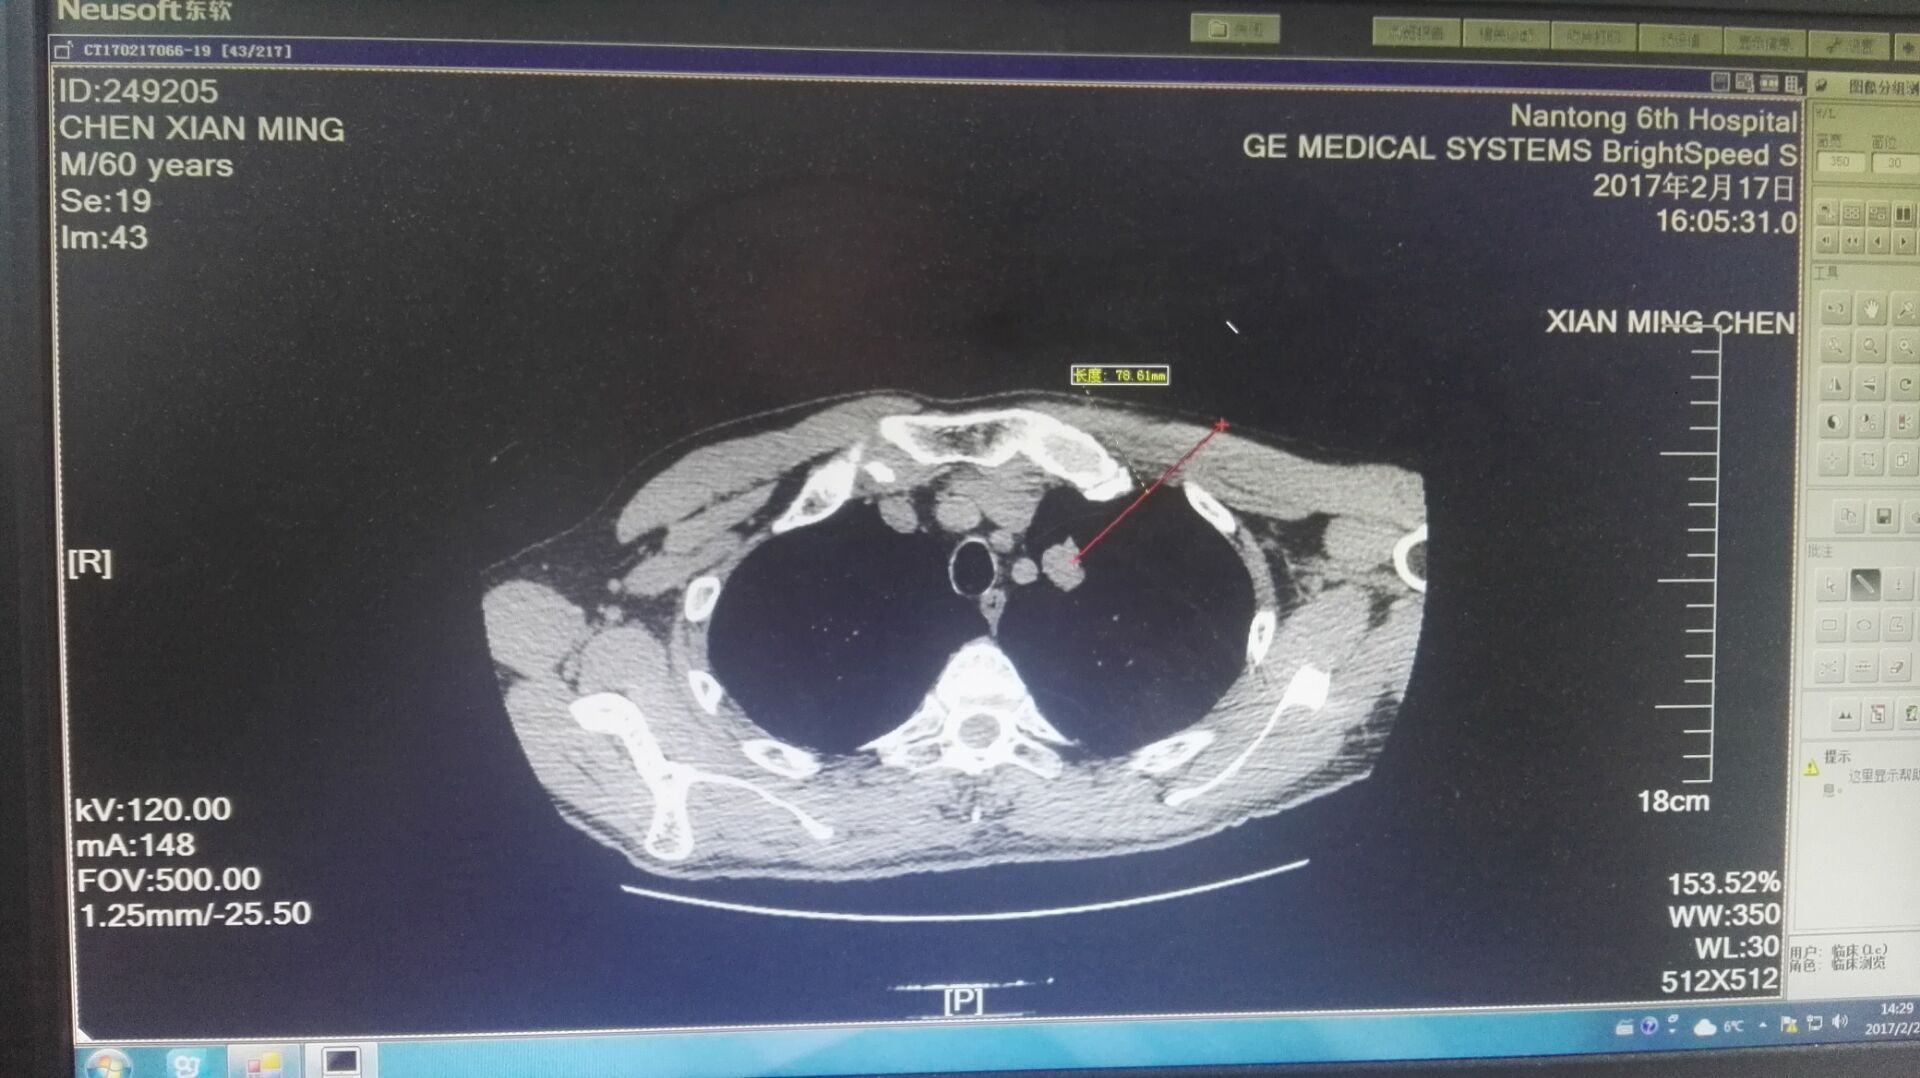

由于患者的肿瘤位置比较特殊,距离左侧颈总动脉仅有3毫米的距离,进行消融时,需要医生精确控制周边的方位,稍有不慎就有可能插入周边的血管,导致上下行神经的损伤,引起术后声音嘶哑、膈肌麻痹和术中心脏骤停等,因而手术难度较大,不能有丝毫差错,不仅考验手术医生的技艺,更加需要麻醉的全力配合。麻醉科主任陈永红说:“术中,因为患者需要保持安静、制动,防止咳嗽、肌肉收缩导致组织撕裂与血管被切割等意外的发生,所以要密切观察患者的生命体征特别是呼吸的变化。”因而,在不插管的情况下,如何良好镇痛也考验着麻醉医生的技术。